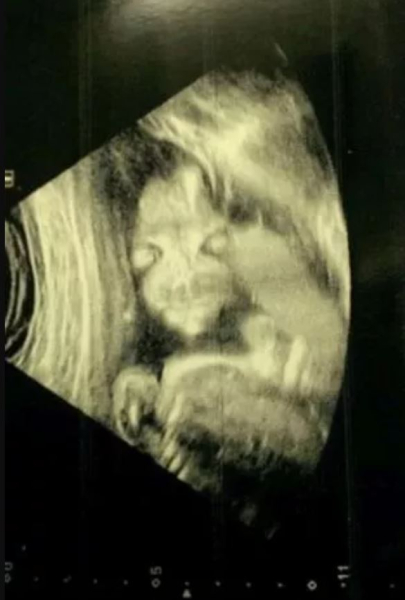

Джейд Бойланд з нетерпінням чекала, аби поглянути на перше зображення своєї майбутньої дитини, але під час УЗД була в заціпенінні, побачивши моторошну фігуру, що нагадує прибульця. За словами матері з міста Чард (графство Сомерсет, Велика Британія) малюк нагадав їй зловісного персонажа з мультфільму “Салатні пальчики”. Про цей випадок пише видання The Mirror.

Майбутня мама з нетерпінням чекала на результати сканування, очікуючи класичний знімок дитини у профіль, щоб потім повісити його на холодильник або надіслала друзям. Але те, що вона отримала, викликало справжній шок. Ненароджений плід на знімку лежав обличчям до неї й мав досить моторошний вигляд, чимось нагадуючи героя мультфільму, намальованого Девідом Фертом.

“Вона була схожою на “Салатні пальчики” з великими очима і довгими пальцями. Жінка, яка робила сканування, почала сміятися. Це мене спочатку злякало, бо ж я не знала, чи все добре. Спитала: “Що таке?”. Тоді лікарка пояснила, що плід повернутий до нас обличчям”, — розповідає Бойланд.

За її словами, друзі та родичі реготали, коли побачили знімок, зроблений ще у 2014 році, коли вона була на 20 тижні вагітності. На щастя, дитина з’явилася на світ шляхом кесаревого розтину абсолютно здоровою. Втім, тоді Джейд провела кілька місяців, несамовито хвилюючись про те, який дівчинка буде мати вигляд після народження.